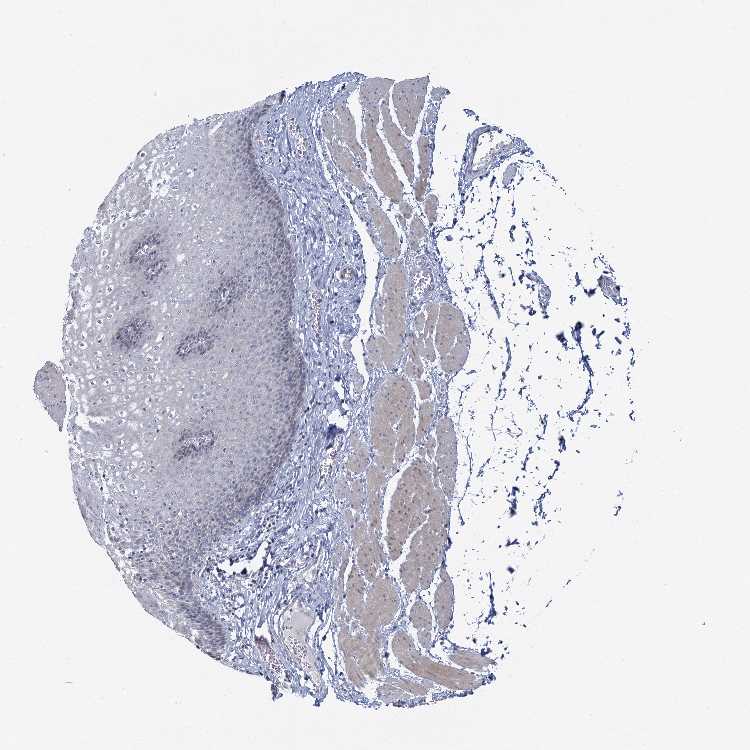

ESOPHAGUS - Antibody stainingi

Antibody staining in the annotated cell types in the current human tissue is reported as not detected, low, medium, or high, based on conventional immunohistochemistry profiling in selected tissues. This score is based on the combination of the staining intensity and fraction of stained cells.

Each image is clickable and will lead to virtual microscopy that enables deeper exploration of all samples and also displays staining intensity scores, fraction scores and subcellular localization as well as patient and tissue information for each sample.

Antibody HPA039081Antibody HPA039082

Squamous epithelial cells Not detectedNot detected